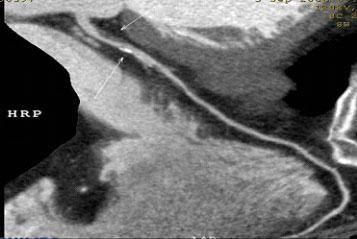

1.冠脈軟斑塊:

2.混合性斑塊:

3.對于斑塊性質的确定,CT優于DSA: